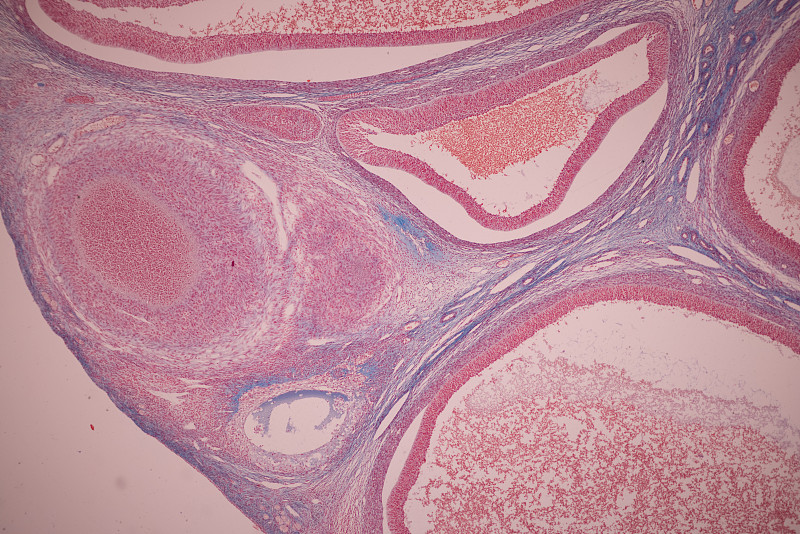

显微镜下的人类细胞详情

JPG